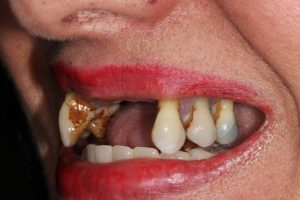

Same Day All on 4 Dental Implants Treatment

This patient had missing teeth and the those that remained were failing. After discussing with the patient, it was decided to remove the failing teeth and rehabilitate with same day all on 4 dental implants.

This treatment is usually carried out in 1 day (after a few preparatory appointments for moulds, x-rays, etc). The failing teeth were removed and implants place on the same day, with a temporary bridge (fixed teeth) attached also on the same day. Following a period of 3 to 6 months, moulds were taken and the definitive bridge placed